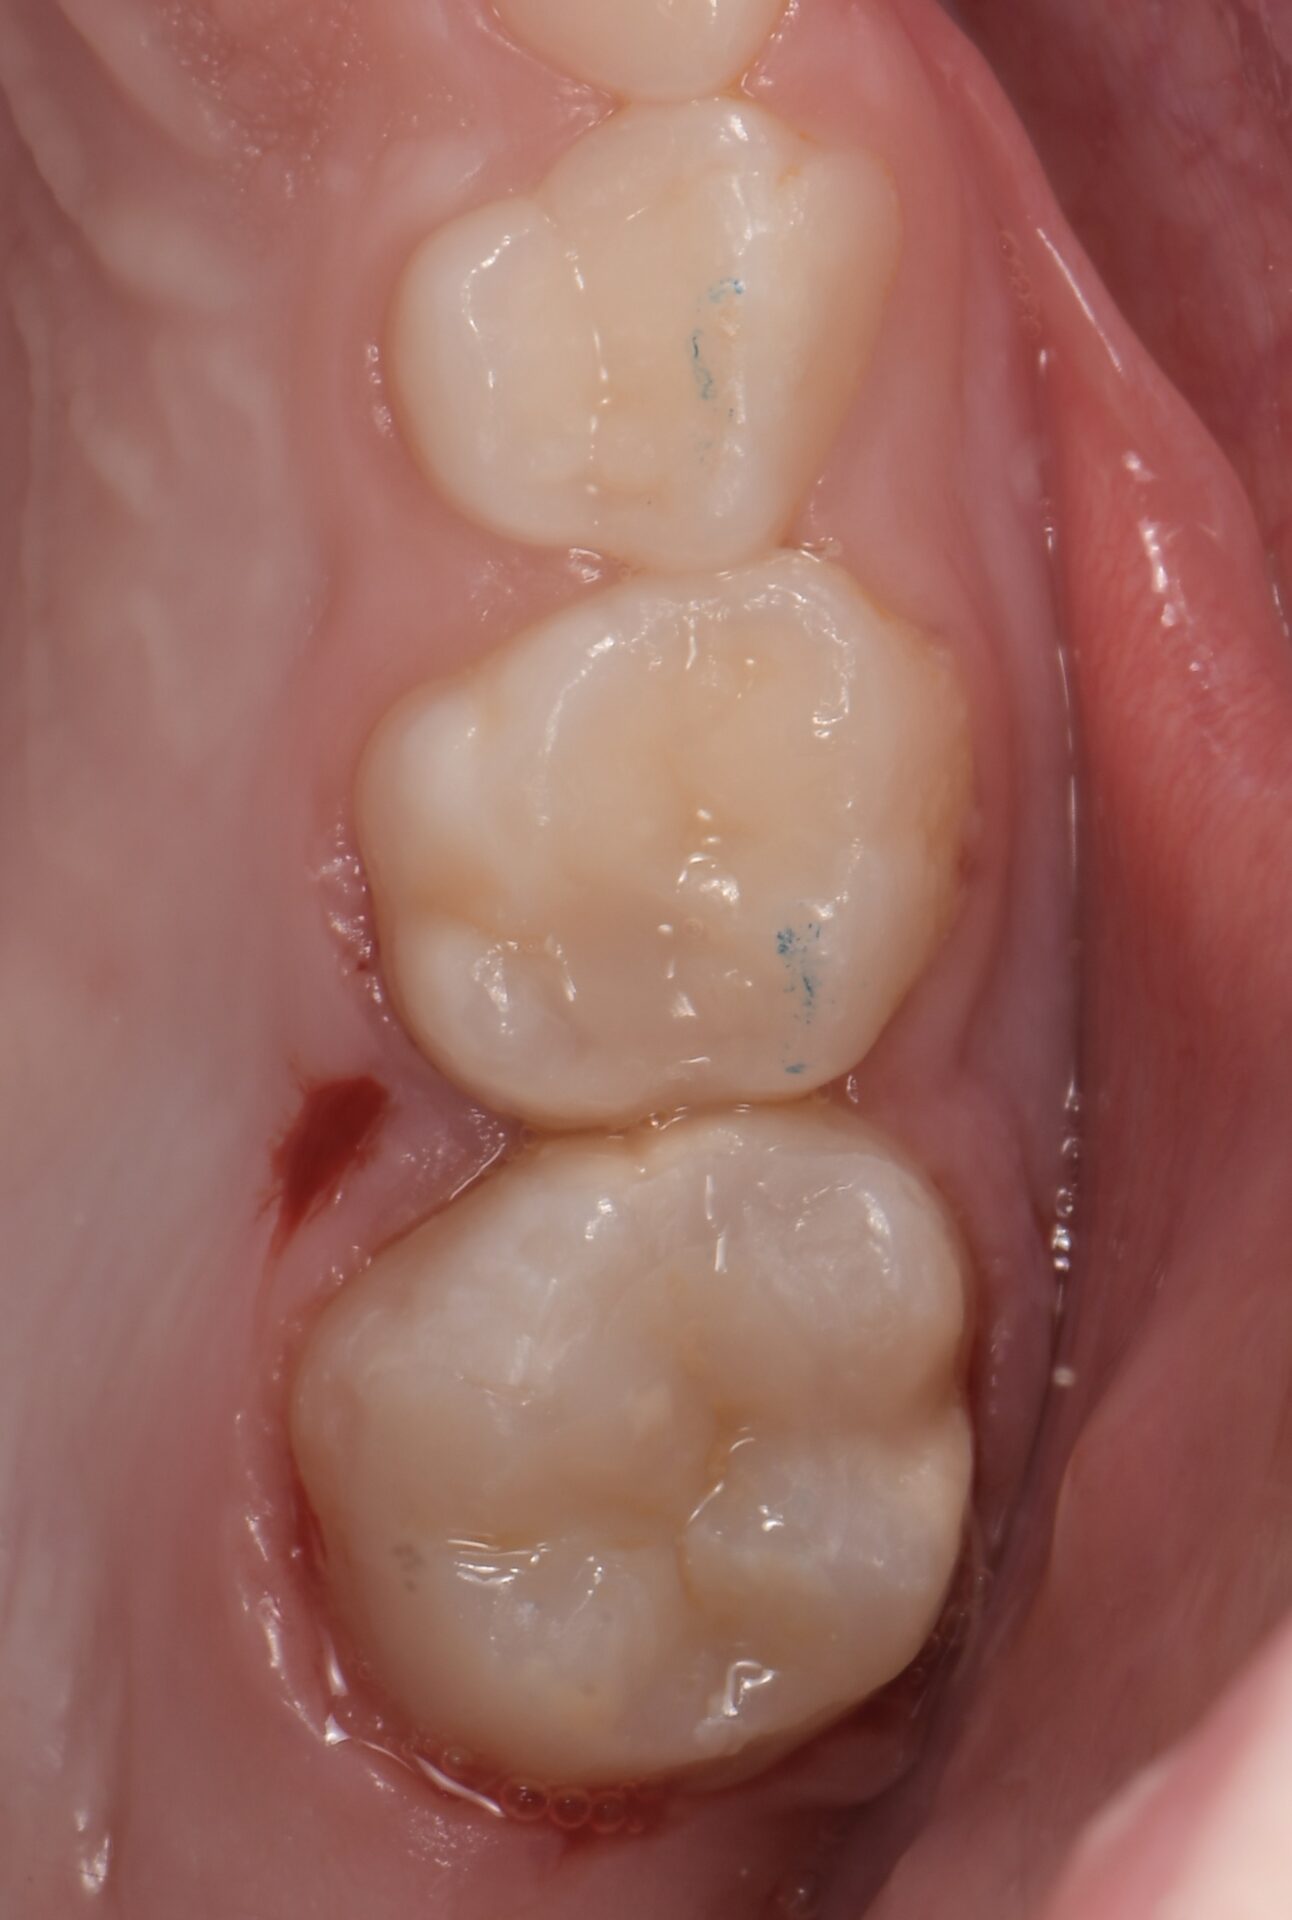

ou indirectes de type onlay en céramique (Figures 13-14-15).

formation dentaire pédodontie Figure 13.

formation dentaire pédodontie Figure 14.

formation dentaire pédodontie Figure 15.

Même si en pédodontie, pour les restaurations indirectes, le composite est assez plébiscité, le fait de réaliser ces onlays directement en céramique, permet non seulement, de ne pas réintervenir à l’âge adulte, mais également de ne pas avoir d’égression passive ou de perte de DV à cause de l’usure prématurée du composite. De plus, si des thérapeutiques d’orthodontie doivent être mises en oeuvre pendant la coirssance, le collage sur de la céramique n’est plus un problème. On notera toutefois qu’une dent atteinte de MIH, n’a pas les même propriétés chimiques qu’une dent saine. Si la composition en elle même reste inchangée, il existe une diminution du contenu minéral (prismes d’émail plus aplatis) et une augmentation du contenu protéique (7). Si des protocoles de collage doivent s’effectuer sur de l’émail non sain, déportéiniser à l’aide

d’hypochlorite pendant 1 min après le mordançage augmente les valeurs d’adhésion.

Figures 13-14-15 : TraitemEnt postérieur par onlay céramique.